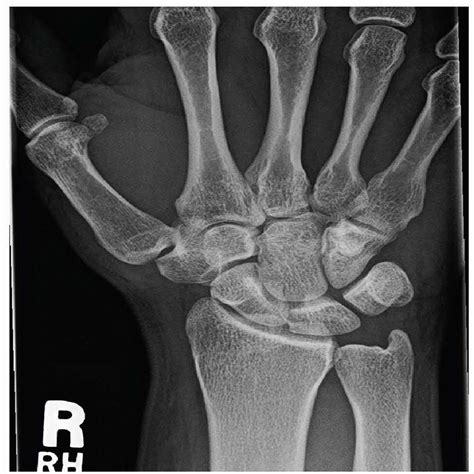

Diagnosis of Hook of Hamate Injuries

Diagnosing a hook of hamate injury typically involves a combination of physical examination and imaging tests. A healthcare provider will perform a thorough evaluation, including:

• Physical Examination: The doctor will assess the wrist for tenderness, swelling, and range of motion. Specific tests, such as the hook of hamate test, may be performed to identify the source of the pain.

• Imaging Tests: X-rays, CT scans, or MRI scans may be ordered to visualize the hook of hamate and identify any fractures or other abnormalities.